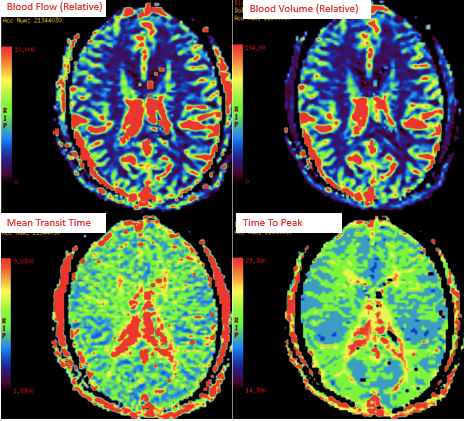

提升医疗技术,满足患者就医需求。医学影像党支部所辖科室积极开新技术,为科室的不断发展注入强劲动力。影像科积极开展了磁共振脑灌注加权成像(PWI)、磁共振波谱成像技术(MRS)、乳腺MRI及动态增强技术、发射型计算机断层扫描仪(ECT)、臂丛、腰丛磁共振成像技术、CT脑灌注成像技术(CTP)、冠状动脉检查技术(CTA)、正电子发射断层-X线计算机断层组合系统(PET-CT)等新技术,超声科为了充分满临床的需求开展了术中经食道超声心动图检查、新生儿颅脑超声检查及超声引下穿刺活检等。

(磁共振脑灌注加权成像(PWI)) (臂丛、腰丛磁共振成像技术、CT脑灌注成像技术(CTP))